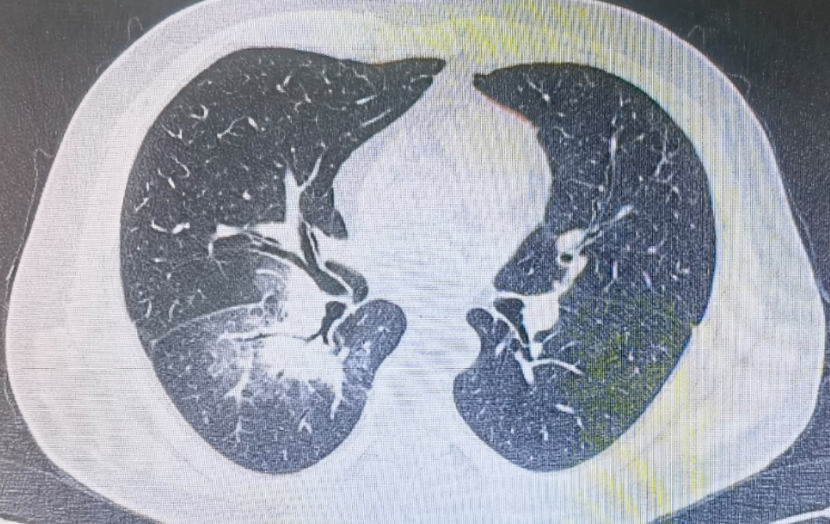

肺部群潘老师分析吸入性肺炎

请问这个患者胸部ct考虑考虑吸入性肺炎